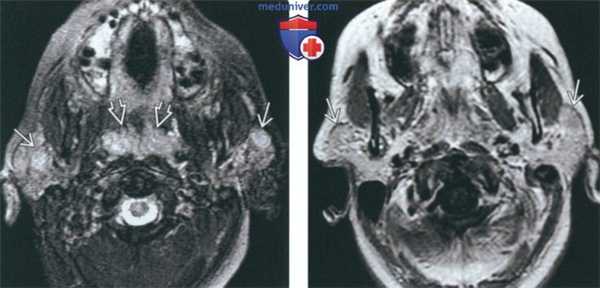

(Слева) Классическая картина доброкачественного лимфоэпителиального поражения околоушных желез при ВИЧ. В обеих околоушных железах обнаруживаются кистозные и солидные лимфоидные образования. Обратите внимание на гипертрофию лимфоидной ткани глоточной миндалины. Реактивная лимфаденопатия (здесь не показана) также весьма характерна для доброкачественного лимфоэпителиального поражения.

(Слева) MPT STIR, аксиальная проекция. В обеих околоушных железах визуализируются лимфоэпителиальные кисты. Обратите внимание, что вовлечены и поверхностная, и глубокая доли желез. Присутствует реактивная лимфаденопатия затылочных узлов. Гипертрофия небных миндалин незначительная.

(Справа) МРТ Т1ВИ FS c КУ, аксиальная проекция. Двусторонние кистозные и солидные образования у ВИЧ-положительного пациента. Небные миндалины гипетрофированы, также имеет место реактивная лимфаденопатия латеральных заглоточных лимфоузлов.

(Слева) На аксиальной MPT (Т2 FS) в обеих околоушных железах определяются объемные образования с сигналом высокой интенсивности. И солидные, и кистозные ДЛЭП характеризуются гиперинтенсивным Т2 сигналом. Обратите внимание на увеличение глоточных миндалин.

(Справа) На аксиальной МРТ (Т1 С+) визуализируются объемные образования в обеих околоушных железах с контрастирующимся «ободком». Солидные ДЛЭП сложнее выявить на исследованиях с контрастом из-за «смешивания» контрастирующихся участков с жировой тканью околоушной железы.